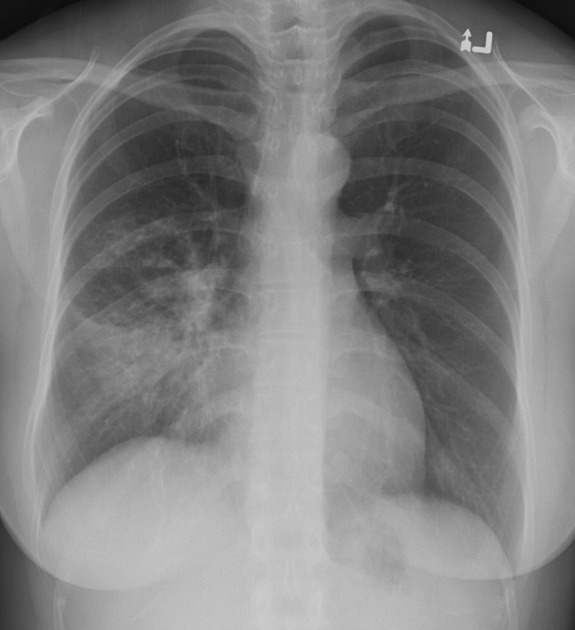

An elderly female patient presented with massive haemoptysis.

A known case of hypothyroidism and HTN and on regular treatment.

Had cough with expectoration and mild streaking of blood in sputum for about 3 days.

Thoughts? Image

Chest X-ray...

Right mid zone homogenous opacity along with the obliteration of both right costophrenic and cardiophrenic angles.

Once stabilized, she was taken for diagnostic fibreoptic bronchoscopy that revealed a cauliflower-like growth in RUL bronchus raising a high suspicion of malignancy.